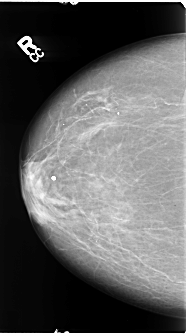

B_3108_1.RIGHT_CC

RIGHT_CC LINES 4704 PIXELS_PER_LINE 2600 BITS_PER_PIXEL 12 RESOLUTION 50 NON_OVERLAY